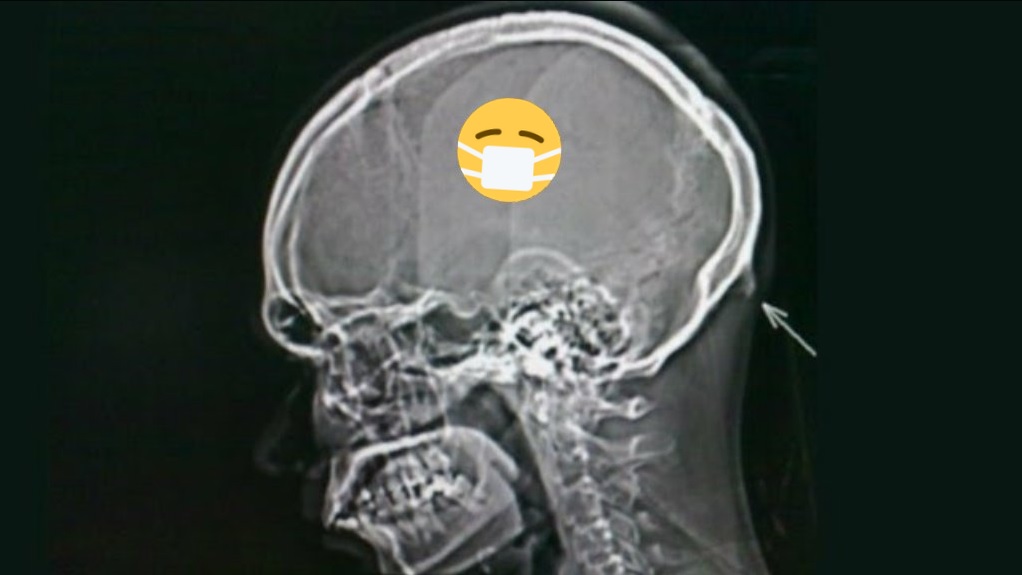

Η υπερβολική χρήση των smartphones οδήγησε στην ανάπτυξη οστού τύπου «κέρατος» στο πίσω μέρος του κρανίου των νέων ανθρώπων, σύμφωνα με έρευνα.

Αυτά τα οστέινα εξογκώματα, γνωστά και ως ενθεσόφυτα, είναι ανώμαλες οσφυϊκές προεξοχές που μπορούν να σχηματιστούν κατά την πρόσδεση ενός τένοντα ή συνδέσμου.

Η έρευνα έδειξε ότι το 41% είχε αναπτύξει ένα κοίλο κομμάτι από 10 έως 30 χιλιοστά στο πίσω μέρος του κρανίου τους. Περαιτέρω δοκιμές, συμπεριλαμβανομένων των μαγνητικών τομογραφιών και των εξετάσεων αίματος, απέκλεισαν την πιθανότητα τα κοκαλάκια αυτά να είναι αποτέλεσμα γενετικών παραγόντων ή φλεγμονών.

Οι ερευνητές εξήγησαν ότι, σε αυτήν την περίπτωση, οι μη φυσιολογικές αναπτύξεις φαίνεται να έχουν προκληθεί από μακροχρόνια πίεση στον σκελετό, καθώς το κεφάλι μετατοπίζεται προς τα εμπρός ενώ χρησιμοποιούμε τα smartphones για παρατεταμένες περιόδους.